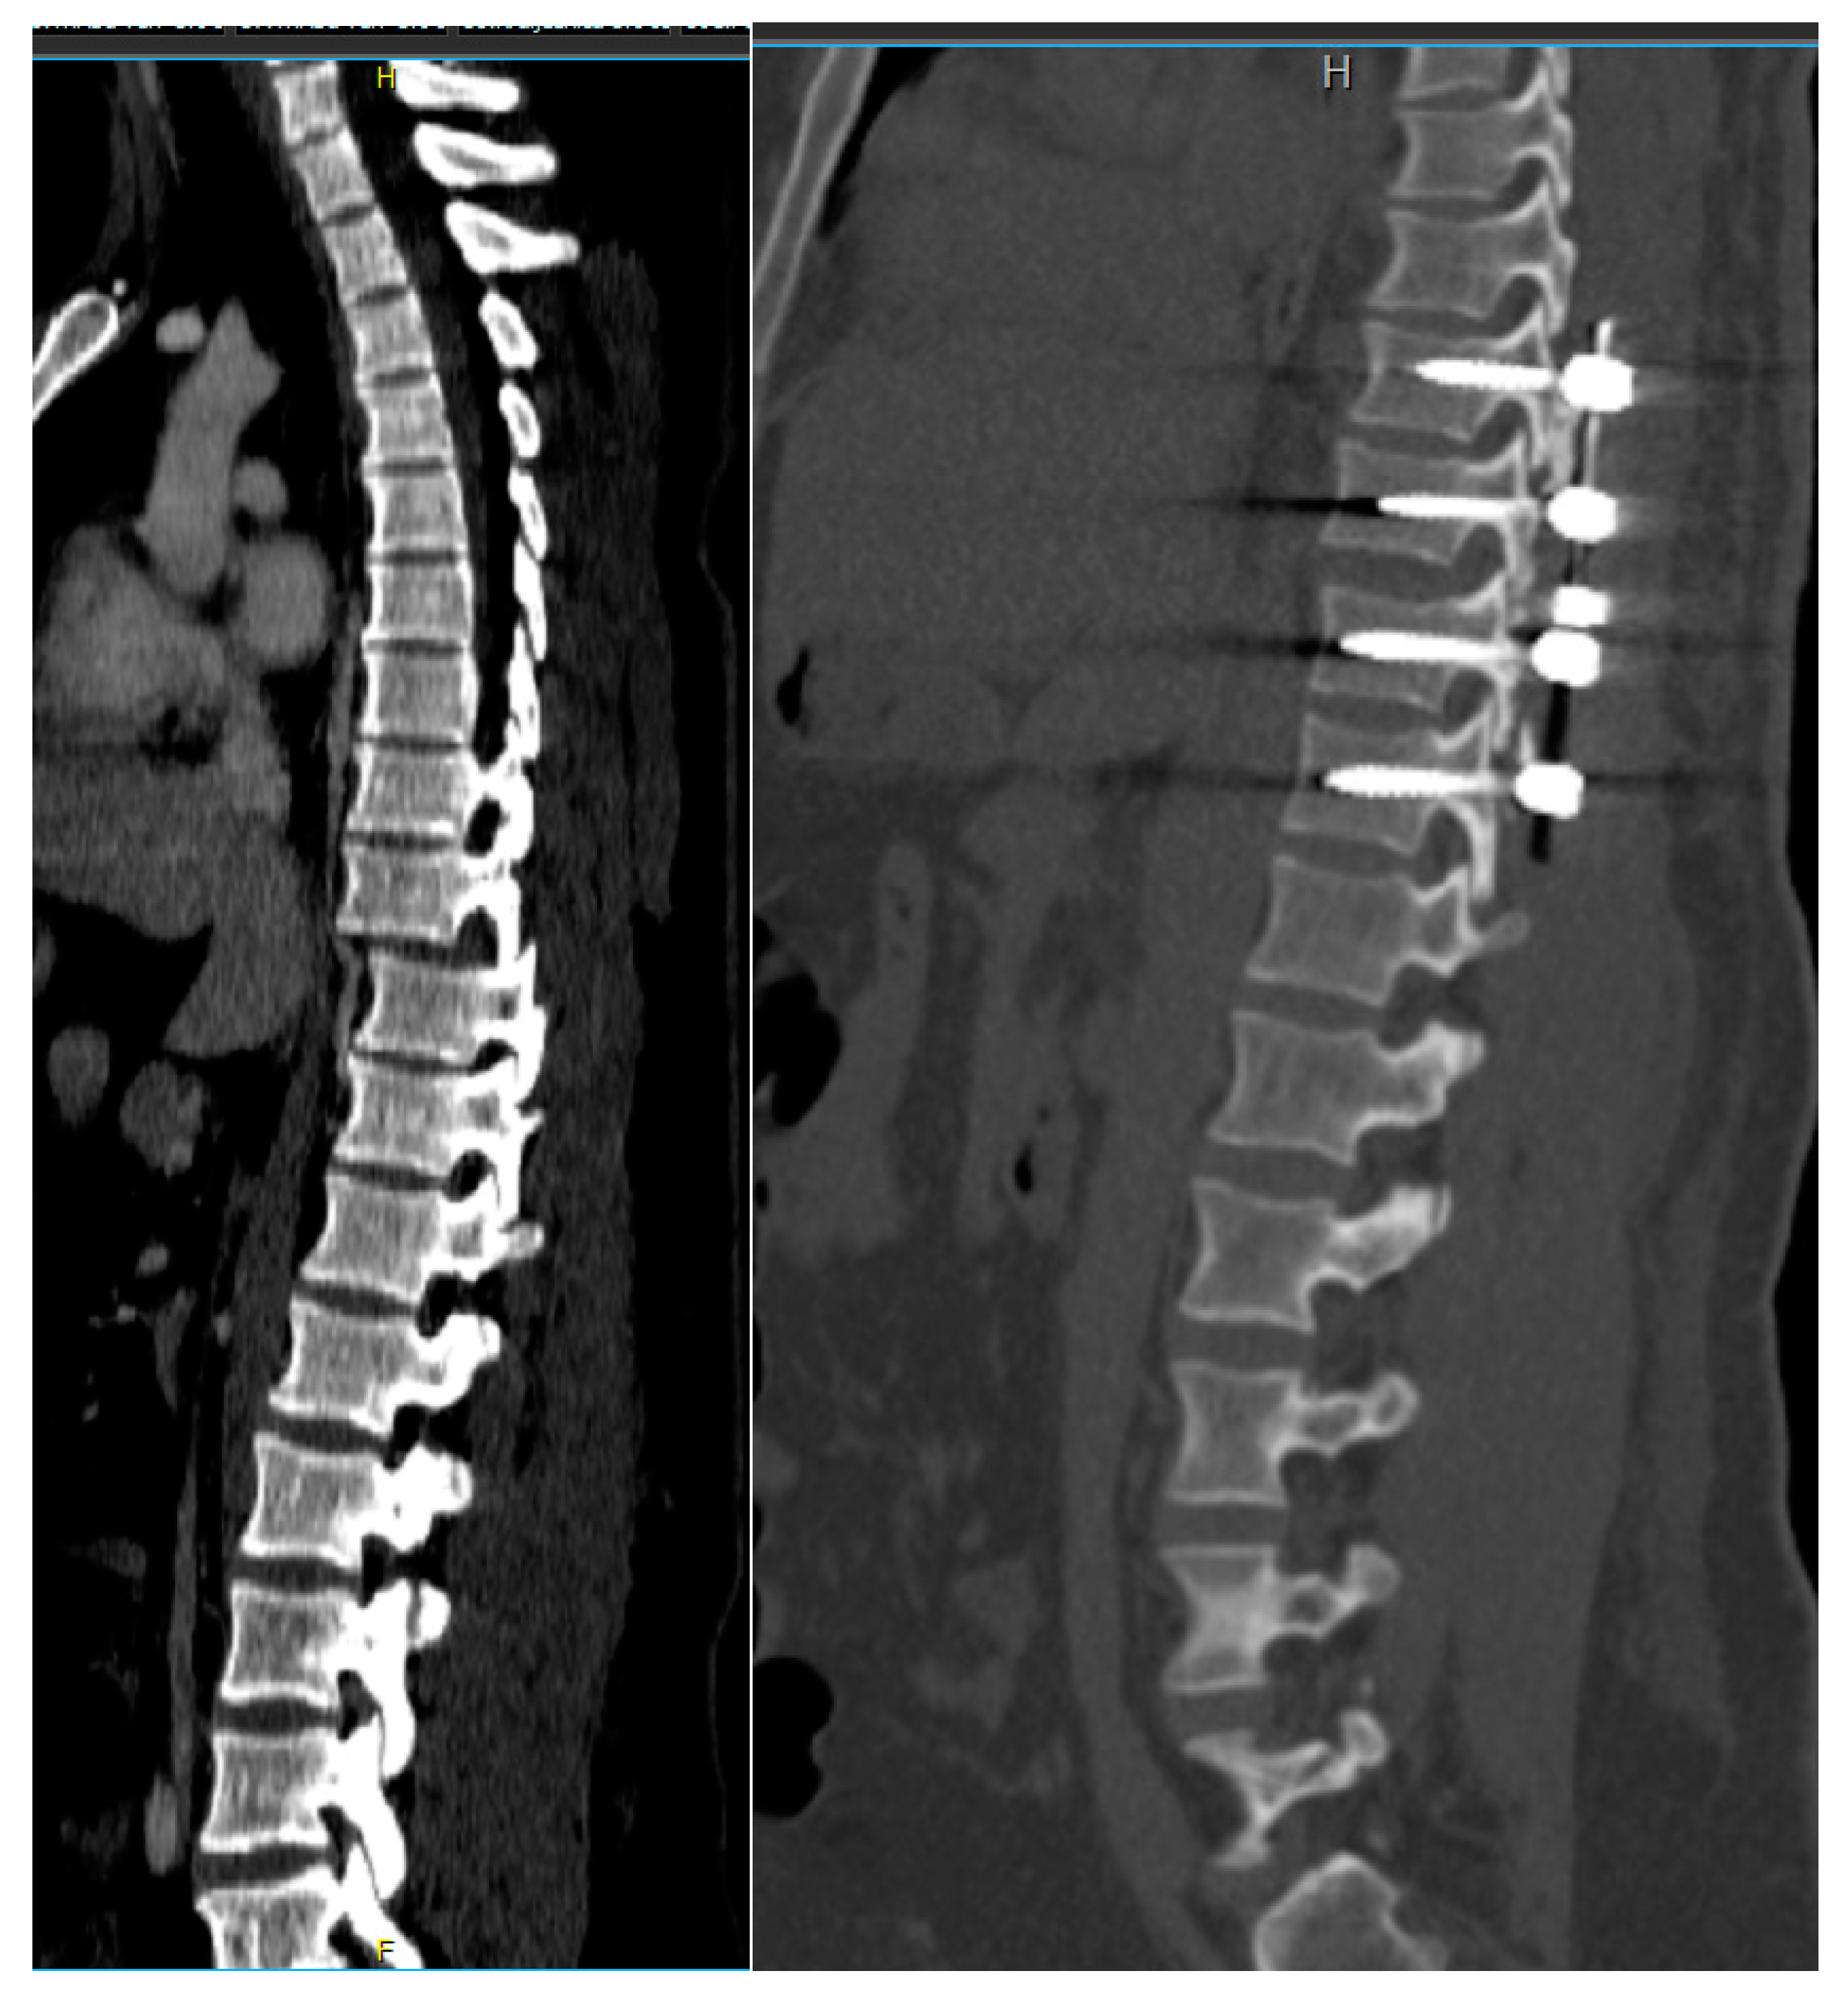

Figure 2. Preoperative CT scan showing a bilateral locked facet fracture dislocation of the Th11-Th12 level. The tips of the superior facet joints were also fractured.